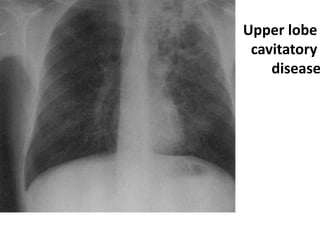

*These chest X-rays show advanced pulmonary

tuberculosis. There are multiple light areas (opacities) of

varying size that run together (coalesce). Arrows indicate

the location of cavities within these light areas. The X-ray

on the left clearly shows that the opacities are located in

the upper area of the lungs toward the back. The

appearance is typical for chronic pulmonary tuberculosis.

*Secondary

tuberculosis.

Some consolidation

in the right upper

lobe with a cavity

(arrowed), typical of

secondary